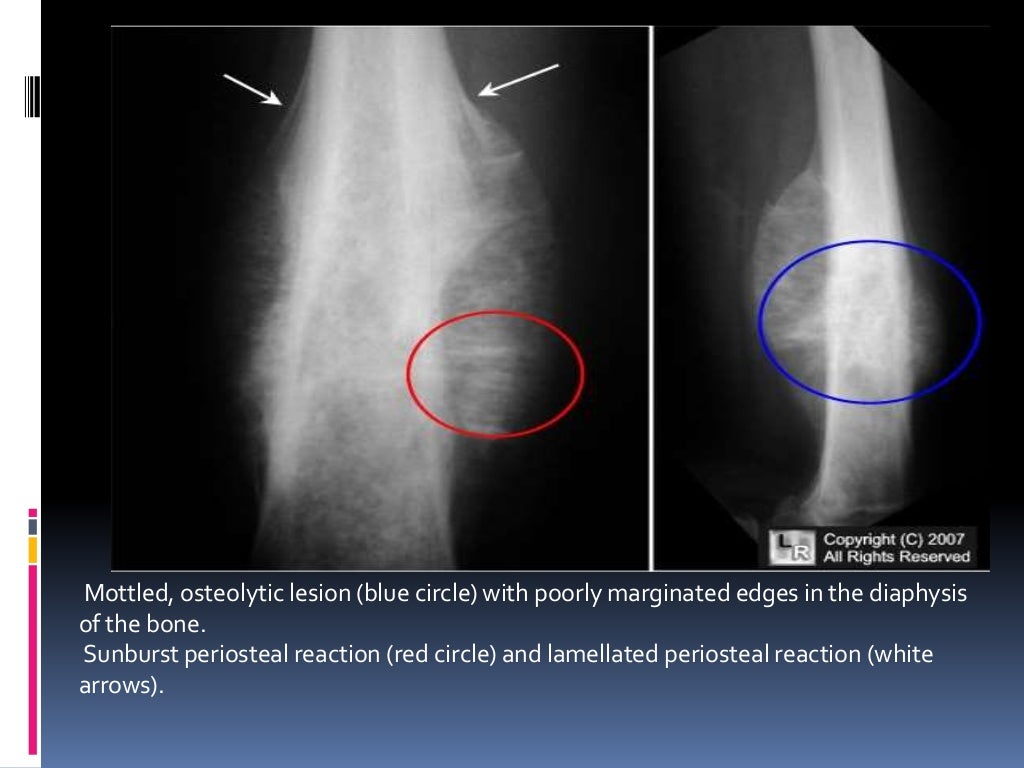

From slideplayer.com